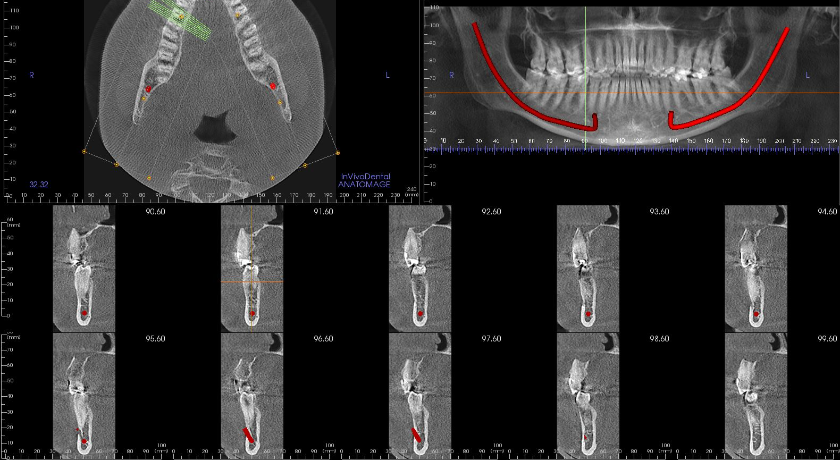

El segundo caso clínico, de Amirbagloy Darian y cols., analiza la retención de segundos molares mandibulares mediante CBCT y sus implicaciones terapéuticas. Se ofrece una visión clara del diagnóstico tridimensional y de la toma de decisiones clínicas en situaciones complejas.